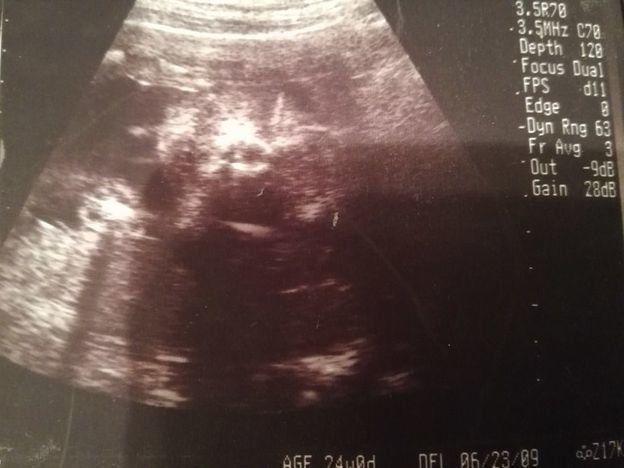

ママにエールさんの妊娠24週目のエコー写真

前回の妊婦検診から3週間後に出血して、この検診の前に慌てて受診したこともありました。原因は、“逆子”になっていた赤ちゃんに子宮を思い切り蹴られていたため。そんなこともありつつ迎えた、定期の妊婦検診。「出血はなくなりました」と先生に伝えたら、「赤ちゃんも逆子じゃなくなっているよ」と先生。ひとまず“逆子”がなおって良かったと主人にメールしました。